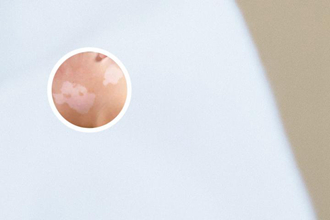

通過皮膚鏡,我們可以看到白斑的顏色變化,這些變化可以幫助醫(yī)生區(qū)分不同類型的白斑。例如,白癜風(fēng)的白斑通常是乳白色或瓷白色,而其他疾病,比如真菌感染,其白斑的顏色可能偏黃色或褐色,而銀屑病的白斑則可能呈銀白色或淡黃色。

皮膚鏡下,還可以觀察白斑的形狀和邊界,這些特征也是判斷白斑性質(zhì)的重要依據(jù)。白癜風(fēng)的白斑通常呈圓形或橢圓形,邊界清晰,而其他疾病的白斑可能呈不規(guī)則形狀,邊界模糊。

皮膚鏡可以放大觀察白斑的表面結(jié)構(gòu),例如毛囊的分布、鱗屑的形狀、血管的走向等。白癜風(fēng)的表面結(jié)構(gòu)通常是光滑的,沒有顯然的變化,而其他疾病可能會出現(xiàn)鱗屑、結(jié)痂、毛囊炎等變化。